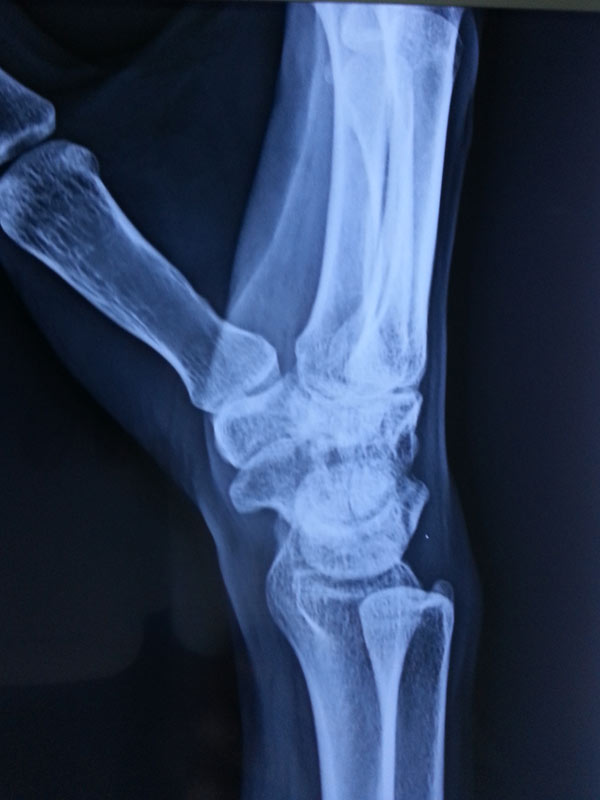

A case of scaphoid non-union

The young, male patient had the fracture of Rt scaphoid/ due to falling on an outstretched hand. The scaphoid fracture was treated, with the plaster cast for 1 ½ month elsewhere. Fracture of Rt Scaphoid was not united. This condition is called, the scaphoid non-union. It was treated with open reduction, and the iliac crest, bone grafting, and K wire stabilization.

Before Surgery